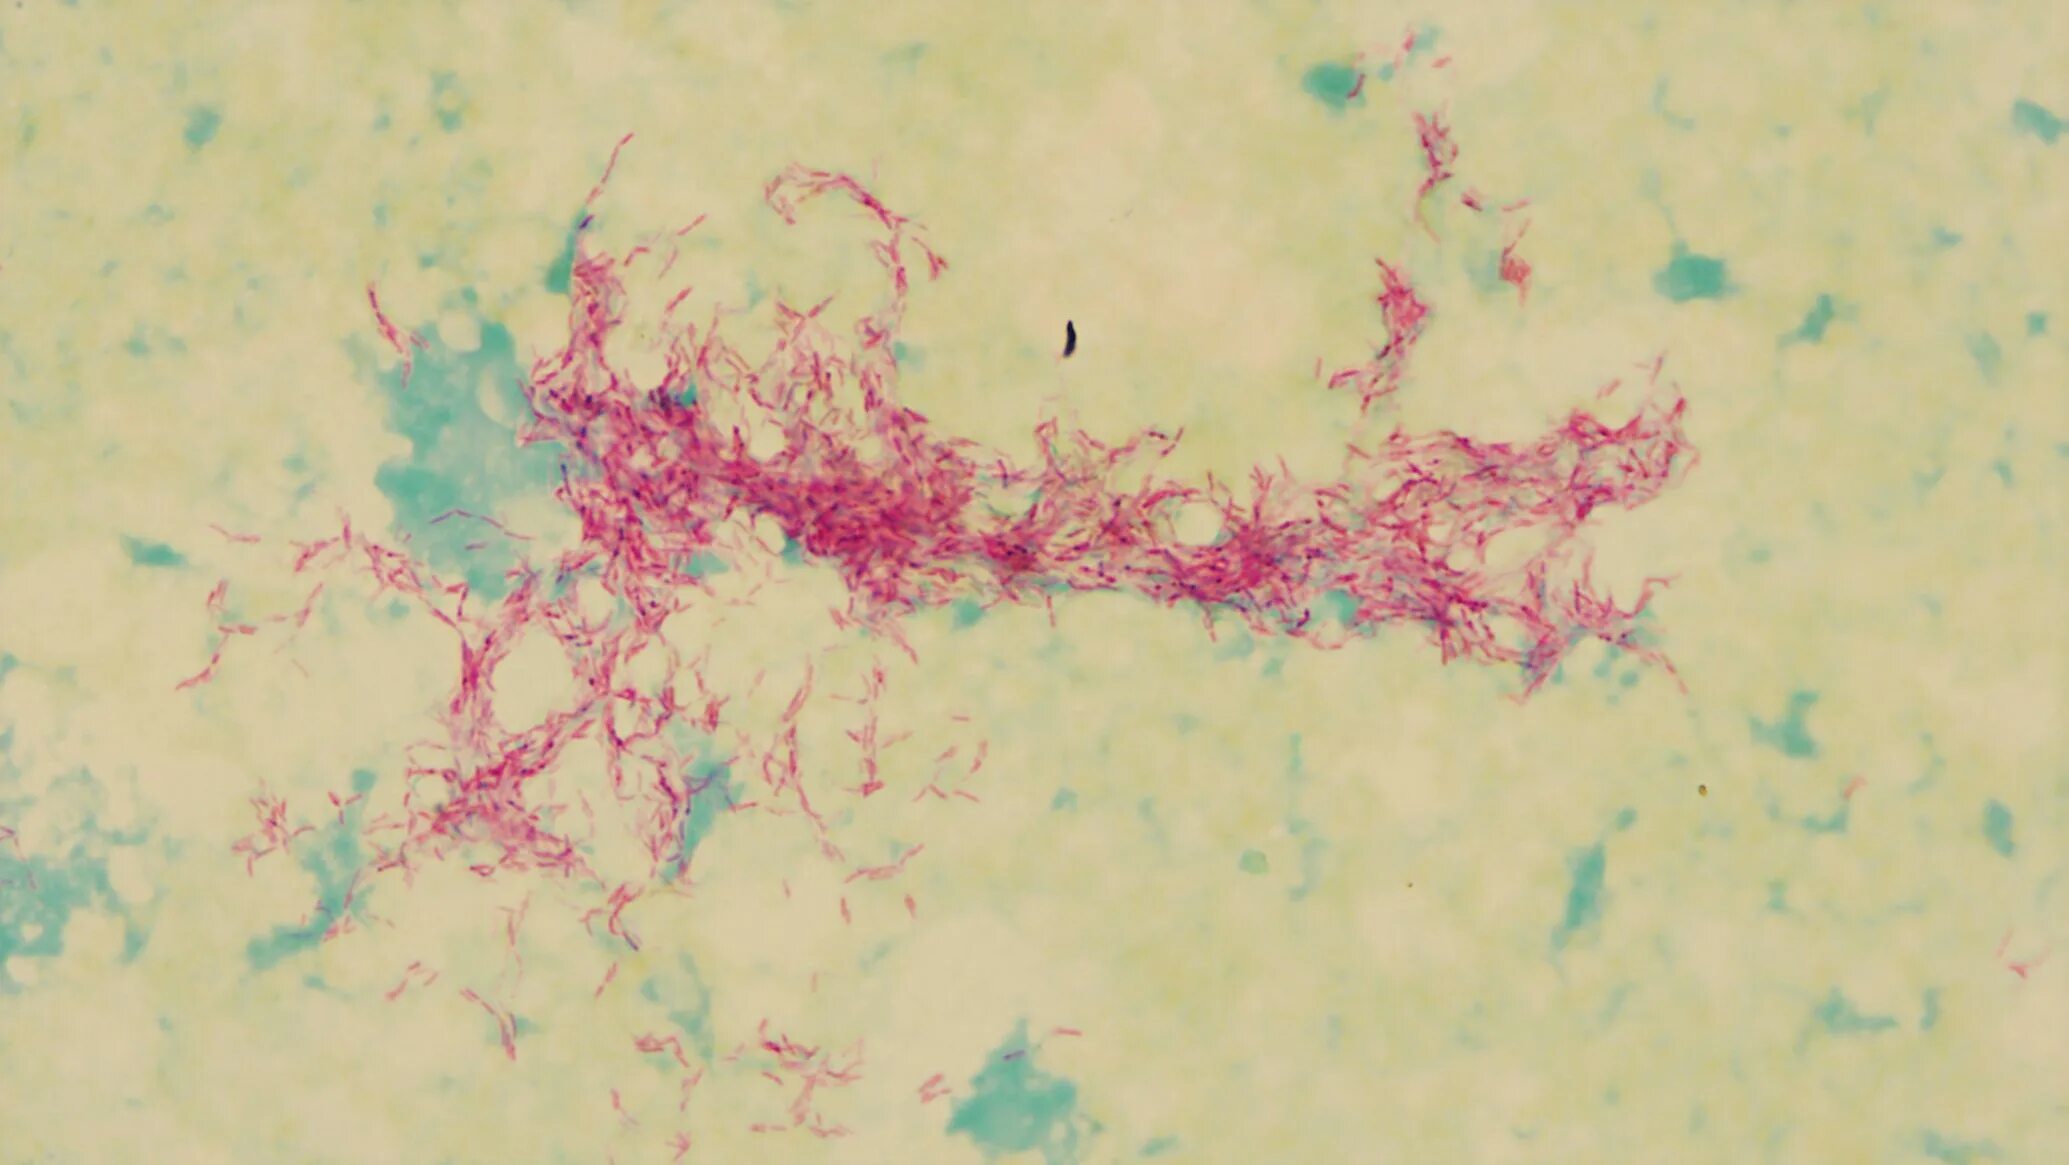

Mycobacterium tuberculosis complex